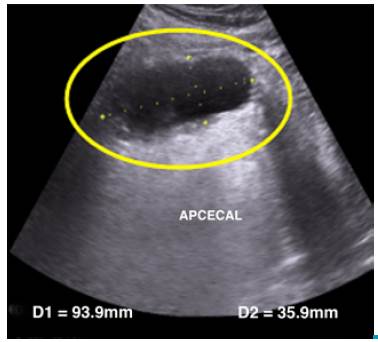

An abdominal ultrasonography was performed, which showed a dilatation of the cecal appendix of 93.9mm x 35.9mm, thickening of the wall and laminar fluid in the right iliac fossa (Figure 1).

Abdominal ultrasound: dilatation of the cecal appendix (circle).

Figure 1: Abdominal ultrasound: dilatation of the cecal appendix (circle).

Source: Own elaboration based on the data obtained in the study.

Laboratory tests may be useful to determine an infectious disease, but not to suspect mucocele. For this reason, it is advisable to perform imaging tests, including ultrasounds, which, in this case, served to observe an elongated and tubular structure (also known as chicken drumstick) compatible with the appendix, with a diameter greater than 1.5cm, a thin wall and calcifications 14. Nuclear magnetic resonance (NMR) is also useful for studying this picture. In this case, ultrasound showed a dilated tubular image, with a diameter of 35mm, which led to suspect appendiceal mucocele, although the result was not conclusive.